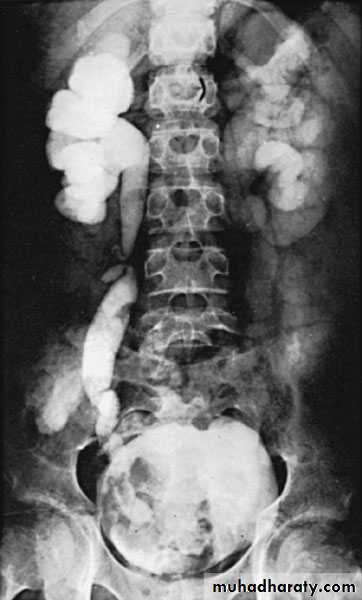

IVU: space occupying lesion, which may be confused with renal tumor.

Retrograde pyelography:

Left renal abscessCT scan: right renal abscess